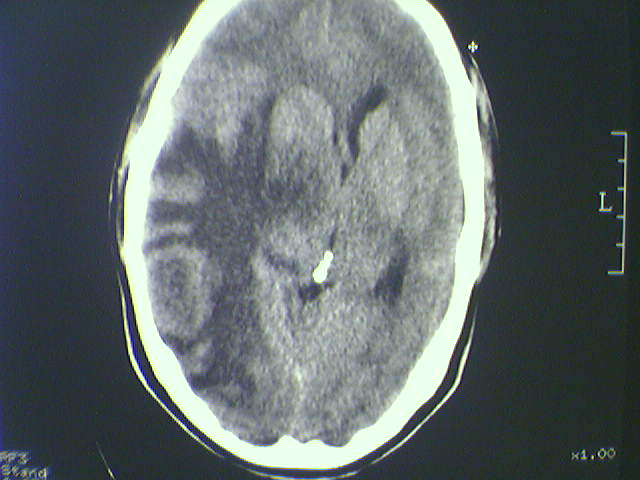

标题: CT21792:男48岁,头痛昏一月加重伴双下肢无力一天,反应迟 [打印本页]

标题: CT21792:男48岁,头痛昏一月加重伴双下肢无力一天,反应迟

病史不详;支持脑转移瘤诊断。

支持脑转移瘤诊断。

多发转移瘤

水肿占位效应明显,支持脑转移瘤诊断

支持 多发性脑转移瘤。